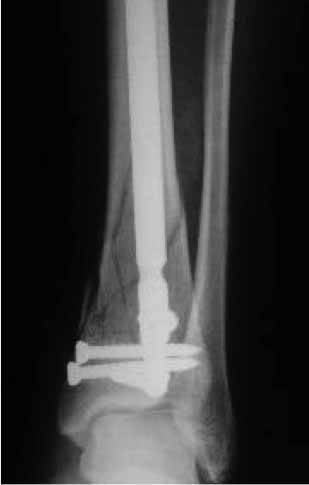

Частота ложных суставов и повторных смещений костных отломков после оперативной стабилизации переломов пилона доходит до 30%. Каждый, кто занимается лечением таких повреждений, наверняка сталкивался с такими осложнениями. Однако лечить такие осложнения в моральном, да и в оперативном плане проще, чем свежие переломы пилона (особенно Ruedi III), поскольку к этому времени становится более или менее понятной судьба голеностопного сустава. Если в достаточной мере владеете блокированным остеосинтезом, то самым оптимальным вариантом, с моей точки зрения, будет следующий. С переднемедиального и латерального доступов выполнить поперечную остеотомию большеберцовой и малоберцовой костей в плоскости параллельной плоскости голеностопного сустава на расстоянии около 3 см от самого сустава. Это минимальное расстояние, которое позволит расположить три блокирующих винта стержня. Важен выбор самого стержня. В данном случае больше всего подходит стержень ChM, имеющий на дистальном конце помимо отверстий в сагиттальной и фронтальной плоскостях и отверстия под углом в 45 градусов, причём на минимальном расстоянии друг от друга. Остетомию и последующую репозицию костных отломков мы выполняем в репозиционном спицевом аппарате. Стержень антеградный. В данном случае не вижу никаких оснований в применении ретроградного стержня, проходящего через здоровый подтаранный и через голеностопный сустав с его до конца неопределённой функцией. Образовавшийся дефект по переднемедиальной поверхности должен быть заполнен костным трансплантатом. Пример похожего случая из нашей практики - в приложенном файле.

Дистальный фрагмент должен быть интересен только в плане его величины (которая регулируется уровнем остеотомии) и способности прочно удерживать блокирующие винты стержня. Безусловно, возникнут трудности при репозиции отломков после остеотомии. Критерий репозиции – проекция центра костномозгового канала проксимального отломка на середину суставной поверхности большеберцовой кости в обеих плоскостях при отсутствии угловых деформаций. И трудность не столько в репозиции, сколько в удержание отломков в репонированном положении на время введения, блокирования стержня и рентгенконтроля. Поэтому мы выполняем такие операции в репозиционном аппарате.

Уважаемый VlaD! А что значит синяя стрелка на Вашей презентации? Проведение одного блокирующего винта через обе кости это принципиальный момент операции?

Слайд взят из собственной презентации по лечению переломов пилона. При переломах пилона в большинстве случаев больше всего подвергается разрушению переднелатеральная и латеральная часть большеберцовой кости из-за вальгусной установки пяточной кости и флексии стопы во время травмы. Поэтому самый дистальный винт, который располагается во фронтальной плоскости, мы, путём ротации стержня, стараемся провести и в малоберцовую кость, чтобы конец блокирующего винта располагался в прочной кости и выполнял свою функцию. Не знаю, насколько это принципиально, но так как обе кости связаны между собой синдесмозом, наверное, в этом есть рациональное зерно.